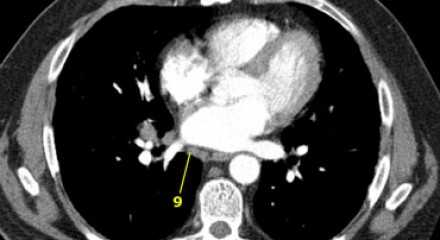

![11]() 7. Подкаринальные лимфатические узлыЭти лимфатические узлы расположены ниже уровня бифуркации трахеи (карины), но не относятся к нижнедолевым бронху и артерии. Справа они располагаются каудальнее нижней стенки промежуточного бронха. Слева они располагаются каудальнее верхней стенки нижнедолевого бронха. Слева лимфатический узел 7 группы справа от пищевода. ![12]() 8. Параэзофагеальные лимфатические узлыЭти лимфатические узлы ниже подкаринальных лимфатических узлов и распространяются каудальнее до диафрагмы. На изображении слева ниже уровня карины справа от пищевода обозначен лимфатический узел 8 группы. На ПЭТ изображении слева показано накопление 18Р-дезоксиглюкозы в узле 8 группы. На соответствующем КТ изображении видно что данный лимфатический узел (голубая стрелка) не увеличен. Вероятность того что в имеется метастатическое поражение данного узла чрезвычайно высока, поскольку специфичность ПЭТ выше чем измерение размеров лимфатических узлов. ![14]() 9. лимфатические узлы легочной связкиДанные лимфатические узлы лежат в пределах легочной связки, в том числе и по ходу нижней легочной вены. Легочная связка представлена дупликатурой медиастинальной плевры охватывающей корень легкого. ![15]() 10. лимфатические узлы корня легкогоЛимфатические узлы корня расположены проксимальнее долевых узлов, но дистальнее медиастинальной дупликатуры и узлов промежуточного бронха справа. Все лимфатические узлы 10-14 групп являются N1 узлами, так как они находятся вне средостения. 1. лимфатические узлы вырезки грудины видны только на этом уровне и выше него 2. верхние паратрахеальные лимфатические узлы: ниже ключиц , справа над пересечением нижнего края левого плечеголовного ствола и трахеи, а слева над дугой аорты